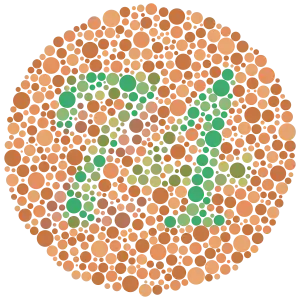

Example of an Ishihara color test plate. The number "74" should be clearly visible to viewers with normal color vision. Viewers with red-green color blindness will read it as "21",[1] and viewers with monochromacy may see nothing. | |

The test consists of a number of Ishihara plates, each of which depicts a solid circle of colored dots appearing randomized in color and size.[3] Within the pattern are dots which form a number or shape clearly visible to those with normal color vision, and invisible, or difficult to see, to those with a red-green color vision defect. Other plates are intentionally designed to reveal numbers only to those with a red-green color vision deficiency, and be invisible to those with normal red-green color vision. The full test consists of 38 plates, but the existence of a severe deficiency is usually apparent after only a few plates. There are also Ishihara tests consisting of 10, 14 or 24 test plates, and plates in some versions ask the viewer to trace a line rather than read a number.[4]

- Transformation plates: individuals with color vision defect should see a different figure from individuals with normal color vision.

Ishihara Plate No. 1 (12)

Ishihara Plate No. 1 (12) Ishihara Plate No. 13 (6)